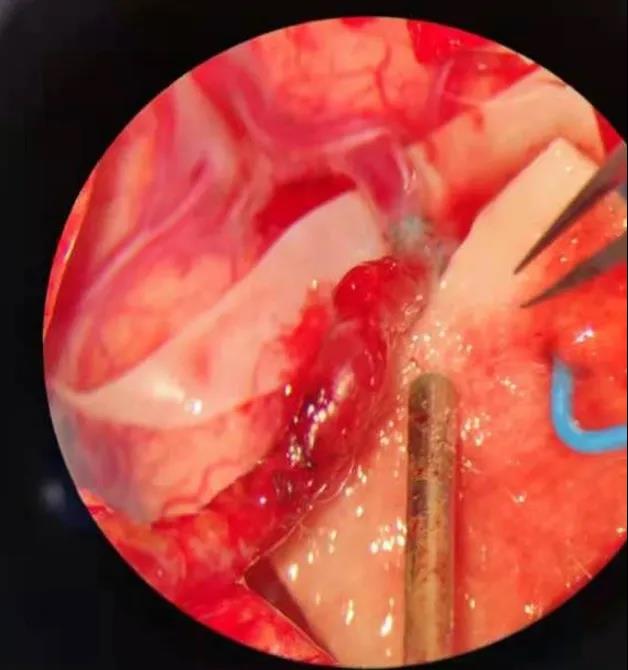

“经过术前造影,我们找到一根管径与颅外颈动脉匹配的大脑中动脉的分支血管作为受体血管,这相当于在颅内进行‘南水北调’”。吴主任慎重考虑,为确保手术风险降到最低,他在科内召开手术讨论,为患者量身制订手术方案,同时脑血管搭桥术因难度极高,风险极大,不仅需要精湛的显微外科技术、高超的血管吻合技术,还需要配套高精尖设备做支撑。

最终在江大附院一体化复合手术室,吴卫江和神经外科介入医生刘晓勇共同配合,打开一个仅有4厘米的骨窗,找到与颅外血管匹配的健康血管,通过造影定位血流供应区域,借助显微镜,吴主任开始端侧吻合,在1.5毫米的吻合口处缝了15针,两根血管成功相接,血流状况良好。

“这就像是在头发丝上跳舞”,吴卫江打趣道:“现在我们等于给大脑重建了一条高速公路,绕过塌方的公路,连接两头”。手术顺利完成,患者立即转入到神经外科监护室进行围手术期的进一步监护治疗。

通过神经外科医疗和护理团队的精心治疗,患者恢复很快。术后复查脑血管造影颅内吻合口很通畅,MRI检查也提示大脑的侧支循环明显增加、脑血供明显改善。